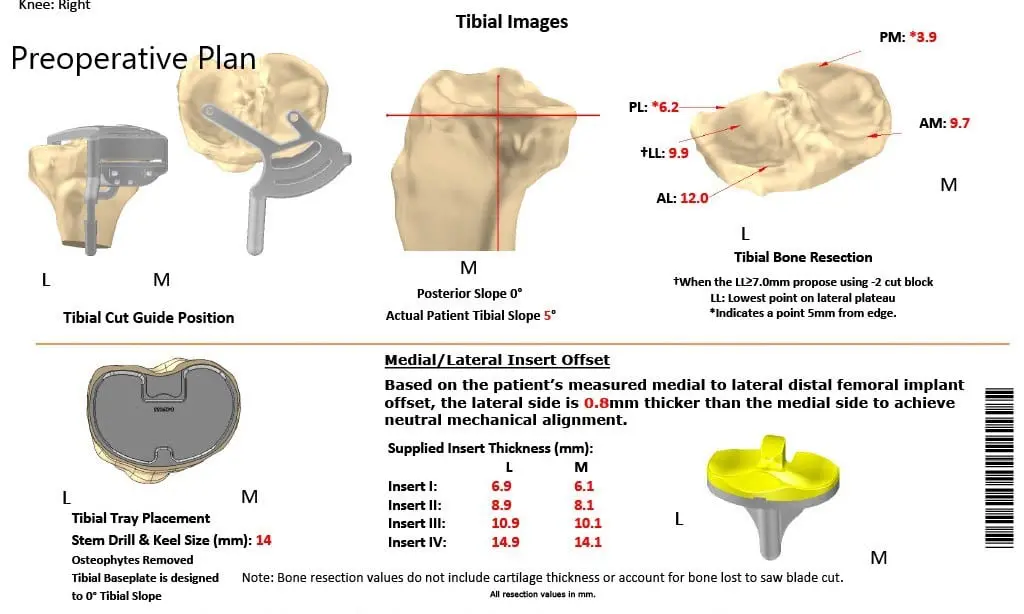

A preoperative CT scan of the right knee including the hip and ankle were obtained a few weeks prior to the surgery. The CT scan images are used to construct a 3D model of the patient’s anatomy. The information from the CT scan was used to create a unique patient-specific implant and instruments.

The instruments which were specific to the patient aided in reducing the amount of bone cut during surgery. The correctly sized patient-specific implant works in unison with the soft tissues of the knee resulting in a more natural feeling knee. The custom knee reduces the need to compromise soft tissues to work with an implant as in the case of off the shelf implants.

Complete Orthopedics patient-specific surgical plan for a custom unilateral knee replacement in a 74-year-old female.